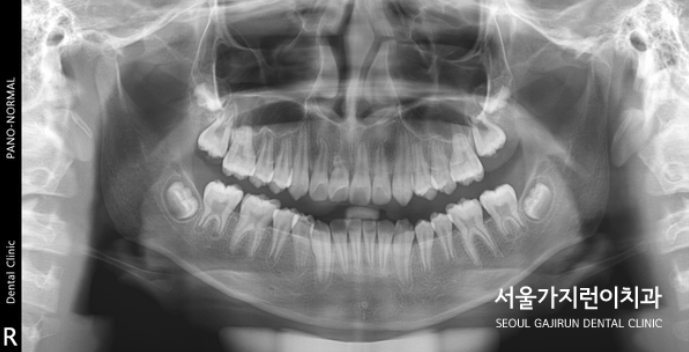

매복된 중절치 치료 결과

위 사진을 보면 달라진 모습을 확연하게 확인할 수 있었습니다. 치근 흡수 없이 가지런한 치아배열이 완성이 되었는데요. 비교적 8세의 나이에 일찍 발견하여 교정을 진행해 좋은 결과를 얻을 수 있었습니다. 만약 매복된 치아가 잇몸뼈와 유착이 심했다면 결국 치아가 내려오지 않았을 수도 있었는데요. 어린 나이에 발견해 유착 가능성이 낮은 탓에 온전한 자리를 찾아볼 수 있게 되었습니다. 상악 중절치와 매복을 비롯한 맹출 장애는 혼합치열기에 흔하게 발견할 수 있는데요. 유치 빠지고 영구치가 나는 시기에 교정치과를 찾아 검진해보면 바르게 성장하고 있는지를 체크할 수 있으니 성장기의 자녀가 있는 가족이라면 유심히 체크해보는 것도 좋겠습니다.